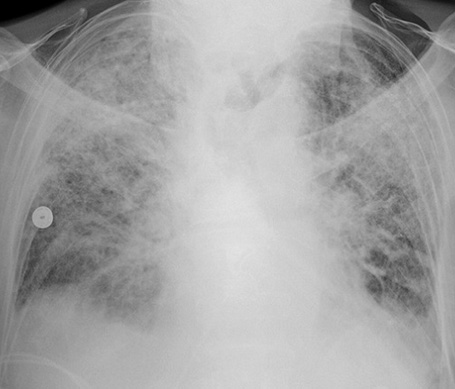

誘發(fā)急性呼吸窘迫綜合征的原因有哪些?在日常生活中有效的了解急性呼吸窘迫綜合征產(chǎn)生的原因,可以幫助我們更好的預(yù)防該疾病的產(chǎn)生,那么下面我們就來給大家介紹一下,一起來看看吧!

(一)肺水腫的產(chǎn)生 各種致病因素使肺血流灌注不足,直接損害肺泡、毛細(xì)血管上皮,引起肺泡毛細(xì)血管膜的通透性增加。血循環(huán)中的粒細(xì)胞、血小板及組織巨噬細(xì)胞釋放的各種炎癥介質(zhì)將加重上述損害。液體及蛋白質(zhì)等漏出血管外,導(dǎo)致肺水腫形成,影響通氣/灌注比率,導(dǎo)致低氧血癥。